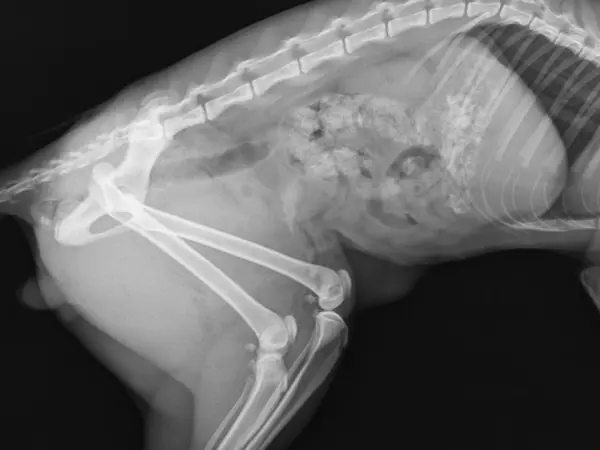

Klinikken tilbyder alt fra sundhedsundersøgelser til kirurgiske indgreb, herunder også røntgen, ultralydsscanning og tandbehandlinger.